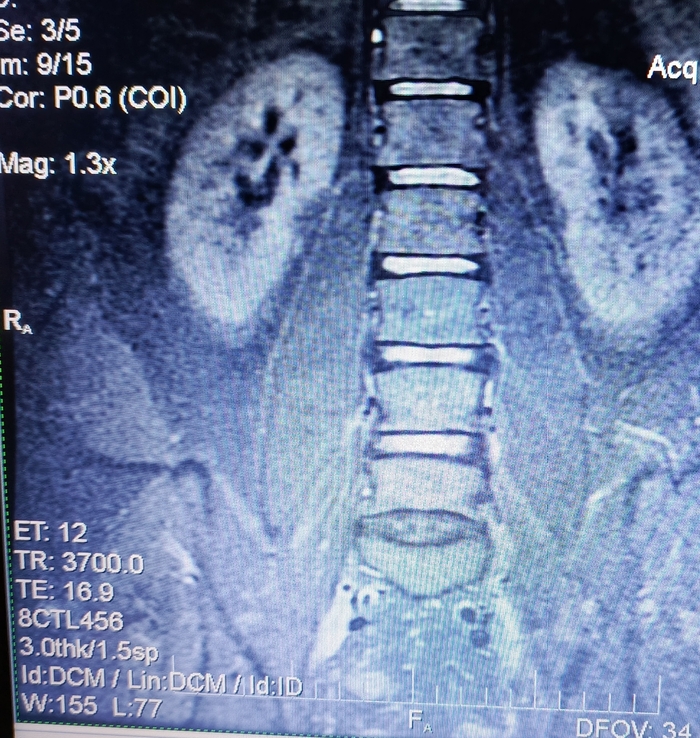

Есть боли в ПОП, в 2020 году на основании МРТ был поставлен диагноз: "Грыжа диска L5/S1. Протрузия диска L4/5."

В 2024 году во время очередного обострения делал повторно МРТ. Диагноз: "Грыжа диска L5/S1. Протрузия диска L4/5. При сравнении с данными 2020 года динамика отрицательная."

2025 год. После очередного обострения и стандартного лечения острая боль прошла, но остались тупые тянущие боли. На днях сделал повторно МРТ. Диагноз: умеренный остеохондроз, с поражением диска L5/S1 с диффузно медианной протрузией.

Собственно вопрос, к тем кто разбирается, действительно ли на данных снимках нет грыжи?

Снимки (с экрана) ниже. Откликнувшихся заранее благодарю.